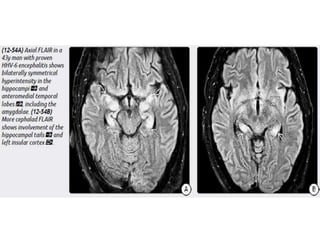

HHV-6 Encephalopathy

Congenital (Perinatal) HIV Imaging Atrophy,particularly in the frontal lobes. Bilaterally symmetric basal ganglia calcifications. Ectasia and fusiform enlargement of intracranial arteries. Strokes with foci of restricted diffusion and subarachnoid hemorrhage may occur as complications of the underlying vasculopathy.